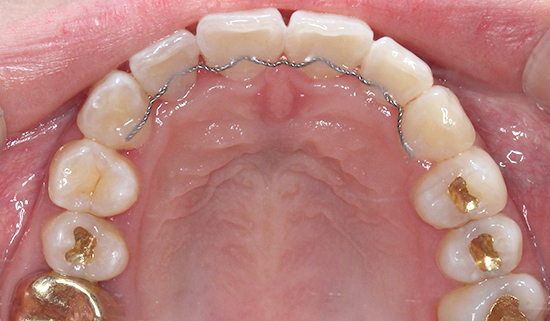

상악 오른쪽 측절치,

사진상으로 왼쪽이

반대로 물리는 반대교합입니다.

간단히 말해 덧니인데

옆에 송곳니와 앞니로 인해

더 도드라져 보이는 상태였습니다.

필요한 공간도 크게 부족하지

않기 때문에 2D교정으로

진행하기로 하였습니다.

[치료계획]

상악 2D교정,

치아모양 수정,

IPR (치아사이공간 삭제)